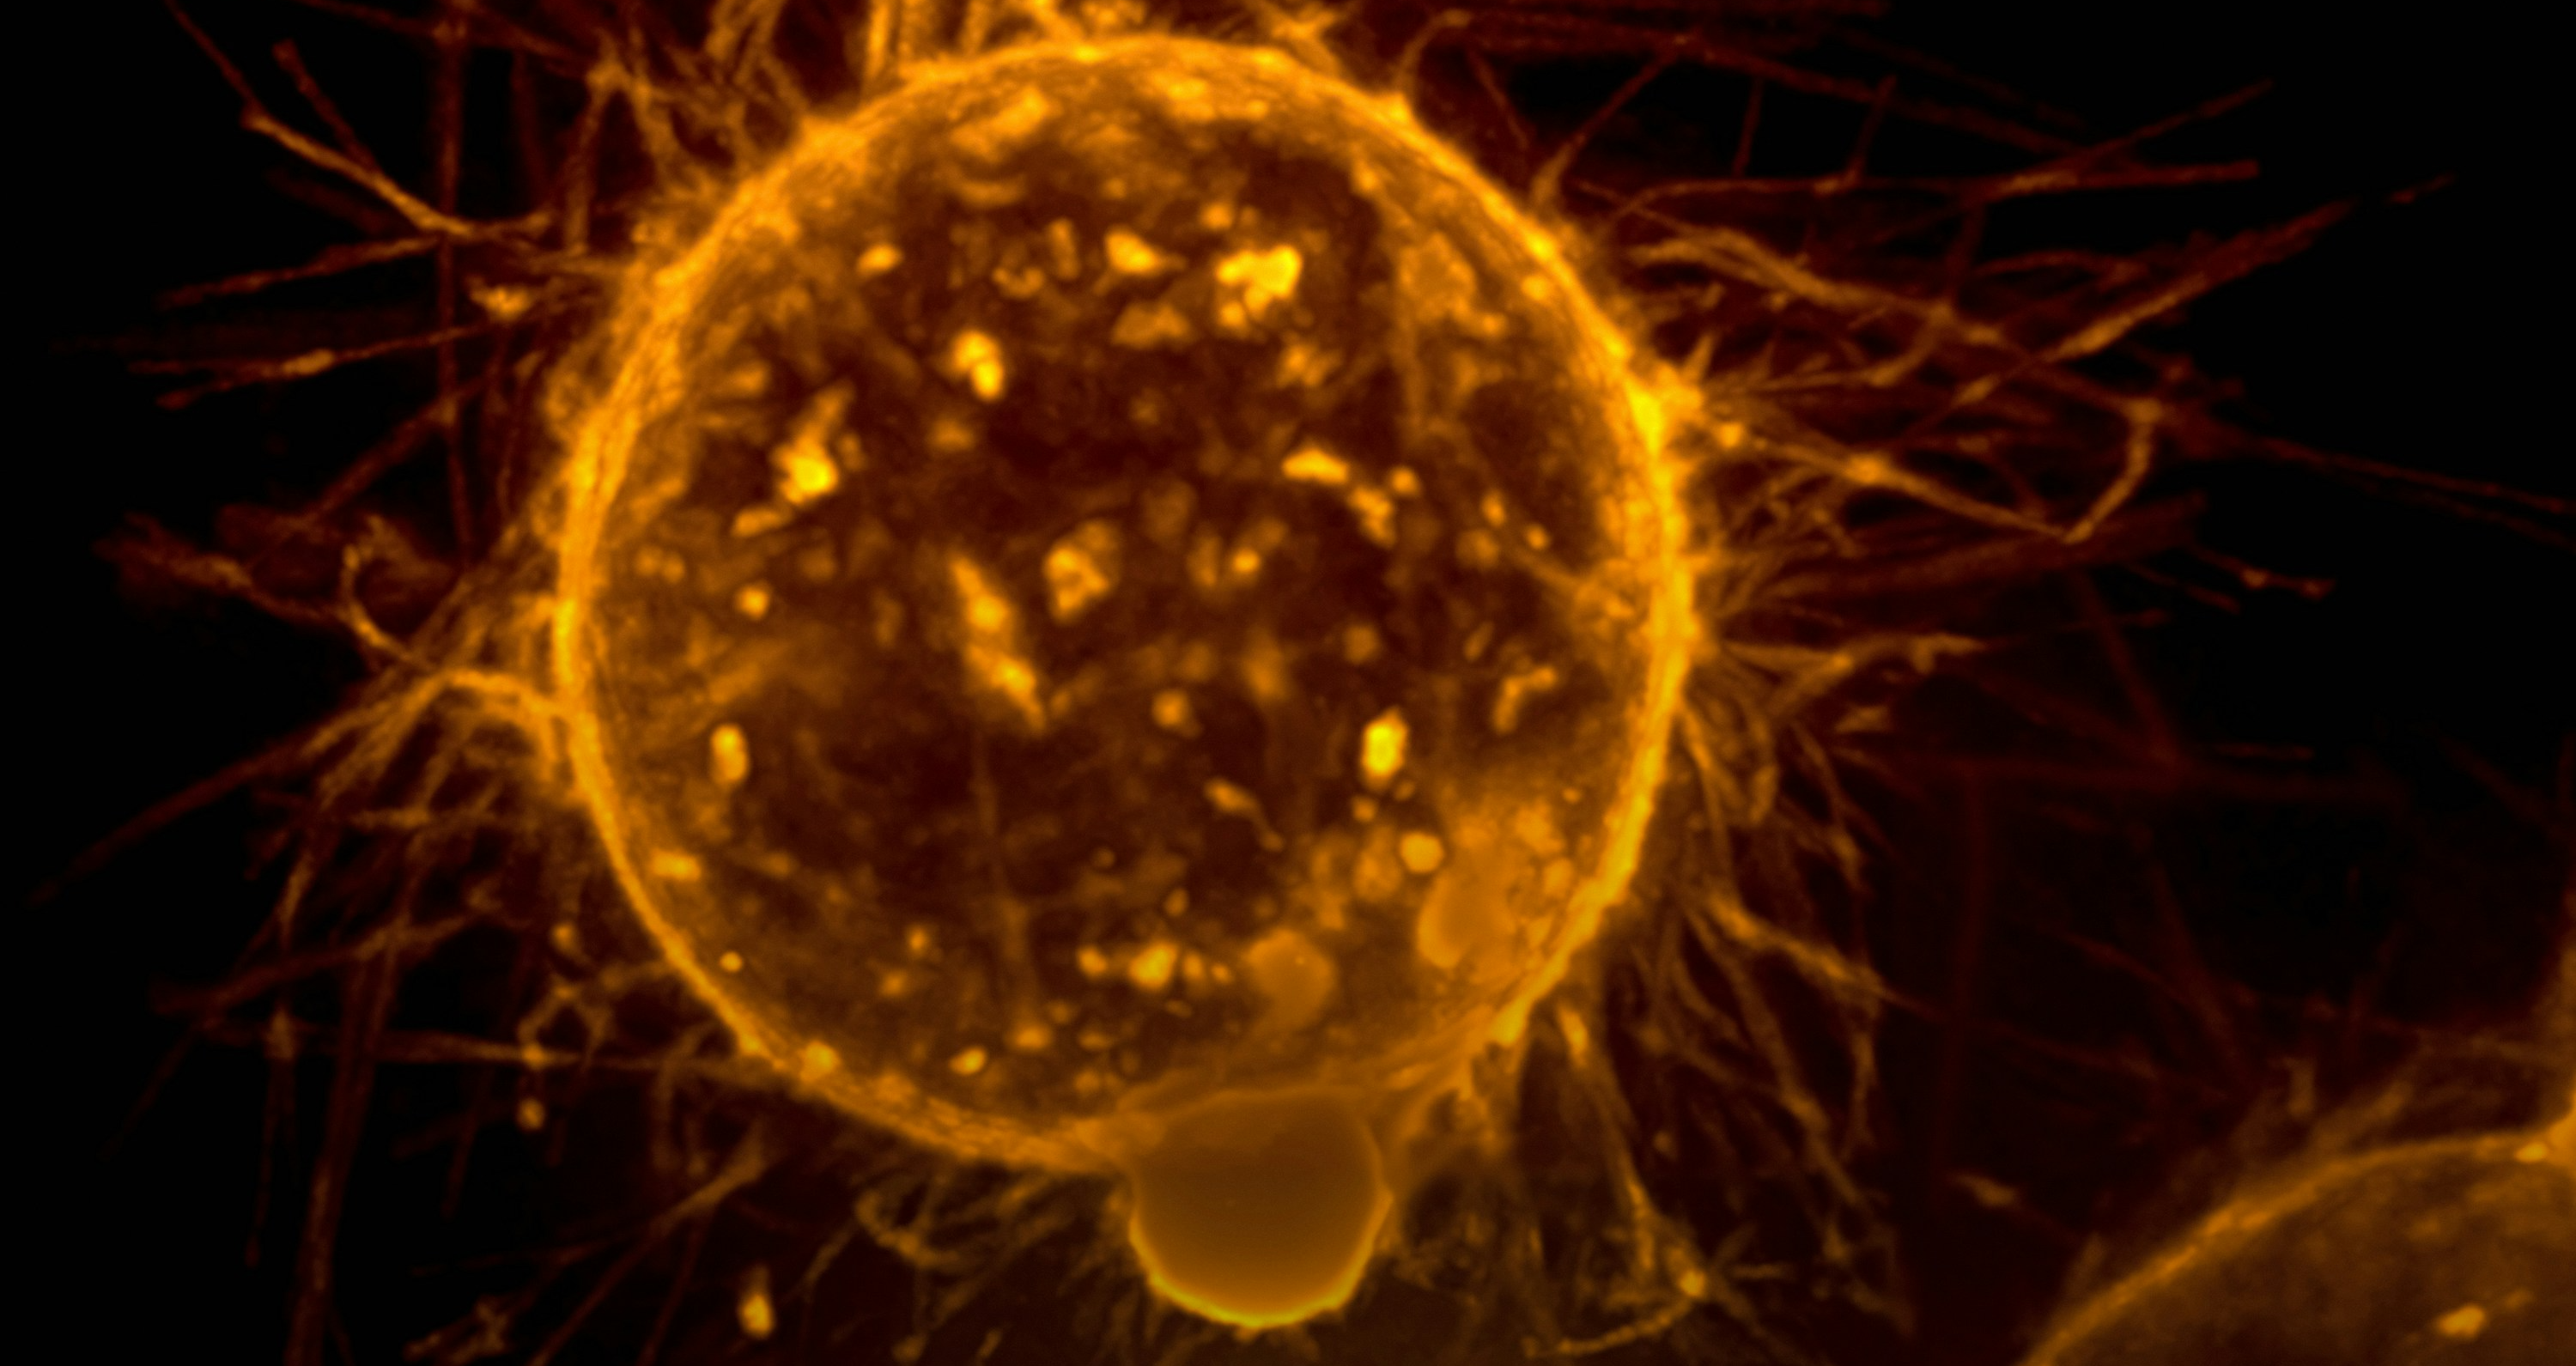

1. 헤포셀루라 암 (Hepatocellular carcinoma, HCC)

- 헤포셀루라 암은 간세포에서 발생하는 가장 흔한 유형의 간암입니다. 주로 간세포의 기능이 손상된 간경변증, 만성 간염, 바이러스성 간염 등의 기저 질환에 의해 발생합니다.

- 헤포셀루라 암은 대부분 간세포 내에서 발생하지만, 때로는 간 외에도 발생할 수 있습니다.